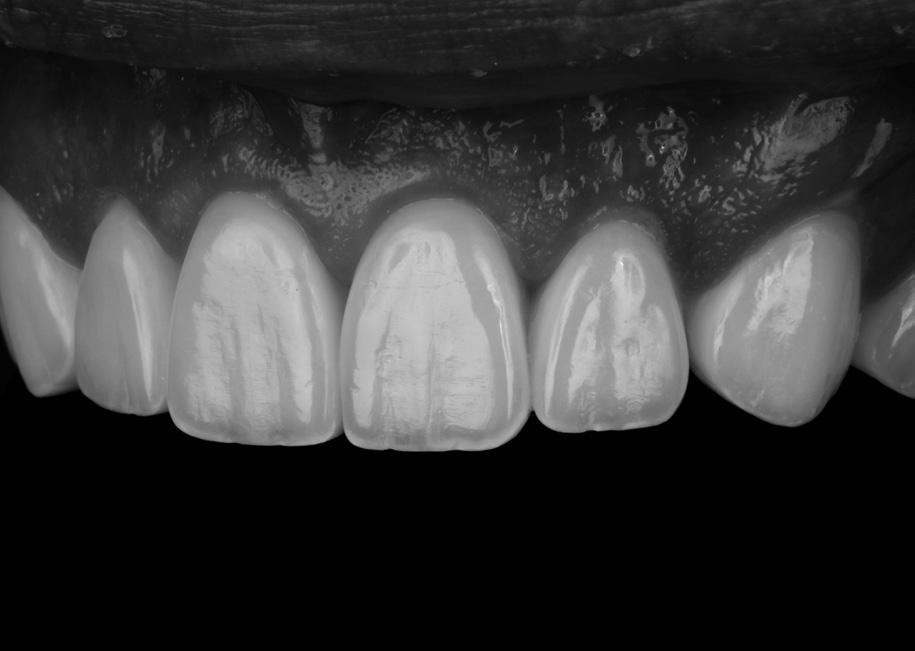

This hands-on course delivers practical training in crafting direct-indirect anterior composite veneers using advanced composite resin systems. Participants will utilize Dr. Fahl’s Polychromatic Layering Technique (PCL) and Structural Color Concept (SCC) on maxillary central incisors to achieve excellent marginal adaptation, anatomical precision, and natural color matching. The course covers composite resin selection, strategic layering with tints and opaquers, and advanced finishing and polishing for seamless integration. Participants will gain handson experience in building and cementing veneers.

Direct composite is quickly growing in popularity among the public because patients are seeking out smile enhancements that are non-invasive and that look believable. When a true “veneering composite” is paired with the Marshall Hanson Method (MHM) for non-invasive smile enhancement, these two objectives are lastingly more fully and universally met than with any other treatment modality or material that I am aware of. What visually sets MHM results apart is the consistency achieved in anatomy, surface texture and polish that so closely adhere to the principles we observe in nature. This hands-on workshop provides a focus on the MHM METHOD-ology that makes these restorations look so REAL!

This workshop will help develop the participants’ composite mirroring skills. Attendees will follow along as Dr. LeSage demonstrates composite layering techniques that create polychromicity, incisal edge halo, and natural incisal translucency. In this workshop environment, microesthetic principles of secondary and tertiary anatomy and attaining an appropriate finish, polish, and luster will be demonstrated.